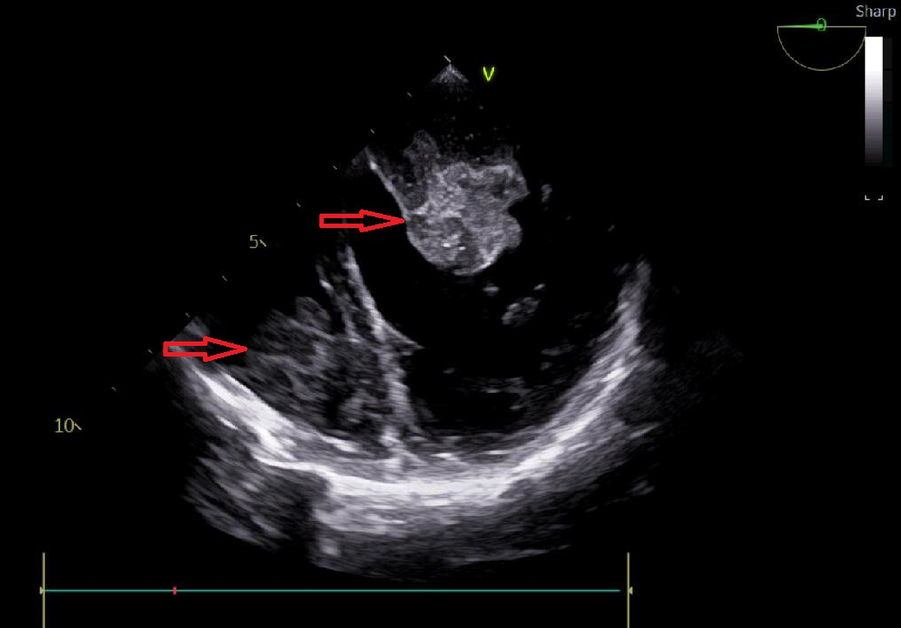

A 25-year-old woman came to our emergency center with repeated chest tightness, palpitations, asthma, occasional hand and foot numbness, and worsening symptoms during daily activities over a 2-month period. Dizziness, headache, nausea and vomiting occurred 1 day before hospital admission. A magnetic resonance imaging (MRI) of the head revealed multiple specks and flaky signals in the left cerebral hemisphere, suggesting the possibility of multiple acute cerebral infarctions (Figure 1, arrow). Intraoperative transesophageal ultrasound demonstrated a soft mass shadow attached to the anterior lobe of the mitral valve, which collided with the left ventricle during diastole. Additionally, another mass shadow was observed at the apex of the right ventricle with minimal activity (Figure 2, arrow below). Subsequently, a dark red jelly-like mass, sized approximately 5 × 3 cm in the left atrium and 3 × 2 cm in the right ventricle, was identified and completely excised (Figure 3). The histopathological examination of a biopsy specimen confirmed the presence of cardiac myxomas (Figure 4).

Figure 2

Transesophageal echocardiography, the mass shadow at the arrow is myxoma.